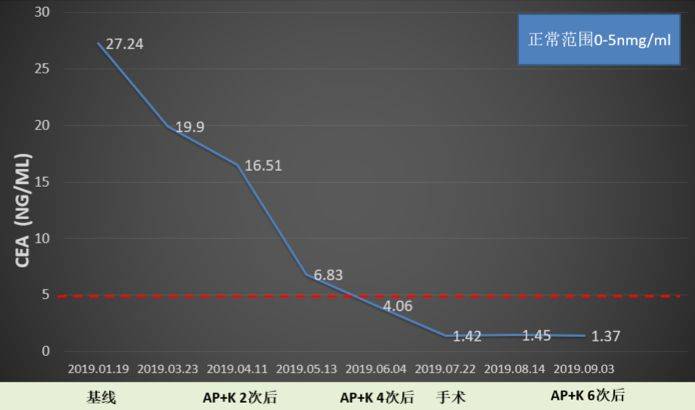

患者治疗至今,头颅转移灶大多已达到CR,肺部肿瘤无明显复发征象,肿瘤标志物在4次术前治疗后一直处于正常范围。后期给予患者培美曲塞单药+pembrolizumab维持治疗。

图8. 患者癌胚抗原(CEA)变化曲线

越来越多证据显示,影像学评估可能并不能很好的体现免疫治疗的疗效。一些探索性研究发现血液生物学标志物,如ctDNA以及肿瘤特异性T细胞扩增,可能是免疫治疗的疗效评价指标。本病例中,肺肿瘤标志物CEA的变化趋势和肿瘤疾病退缩的一致性很好,提示肺肿瘤标志物也可以作为免疫治疗评价的一项简单的血液学指标。